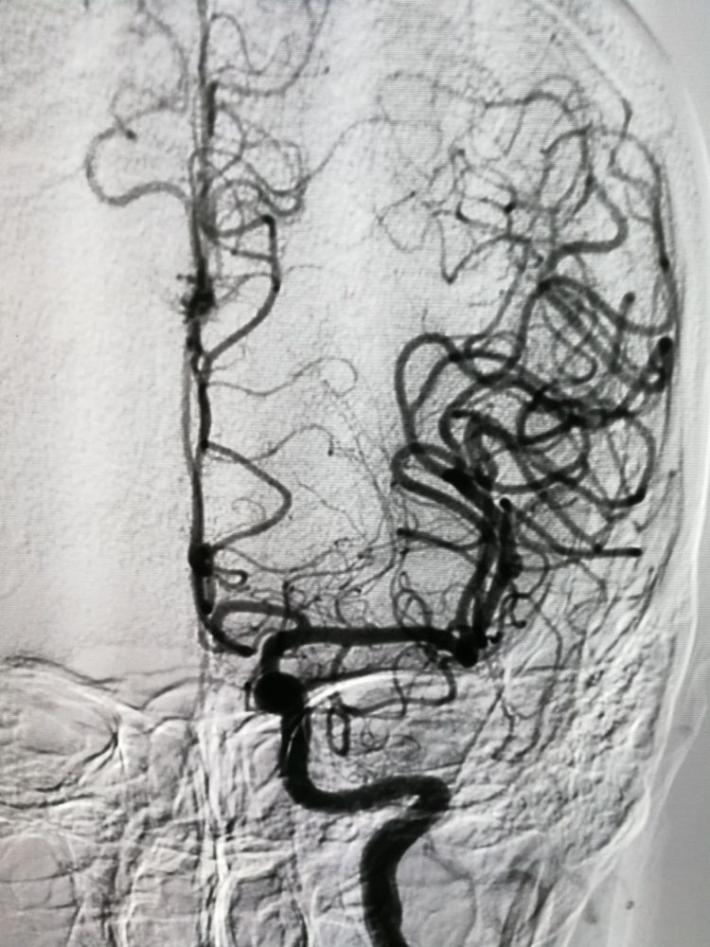

发病后6天(入院当天)DSA示:右侧前交通动脉瘤,右侧脉络膜前动脉瘤,仔细阅片,认为责任动脉瘤为前交通动脉瘤可能性大。原因如下:前交通动脉瘤约2x3mm大小,形状较狭长,瘤顶指向右侧前下方(也可解释蛛血部位)。而脉络膜前动脉瘤约1×1mm大小,形状较扁平,破裂可能性相对小些。

右侧翼点入路,解剖脑池系统,见前交通动脉瘤向右前伸入右侧视神经下方。予以夹闭。

显露诸血管正常。

探查右脉前小动脉瘤,未破,予以包裹。手术完毕。